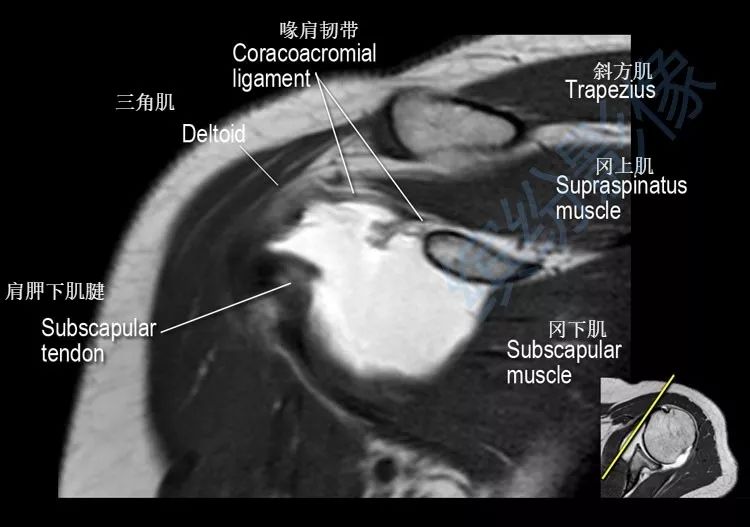

肩关节斜冠状面mr断层解剖